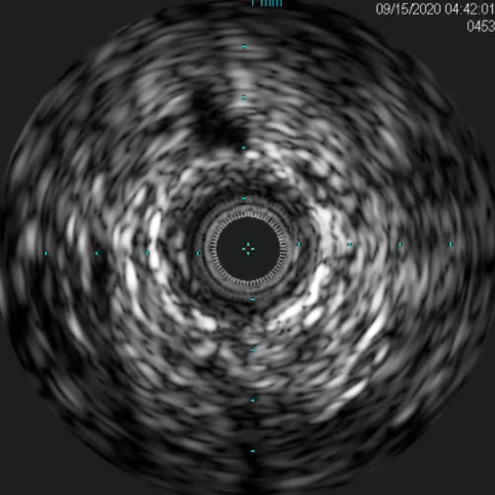

术后评估

造影显示:胫腓干动脉血流恢复通畅,支架形态及位置理想,胫后动脉显影较术前明显改善;

腔内超声证实:铁支架完全张开、贴壁良好,无明显残余狭窄。